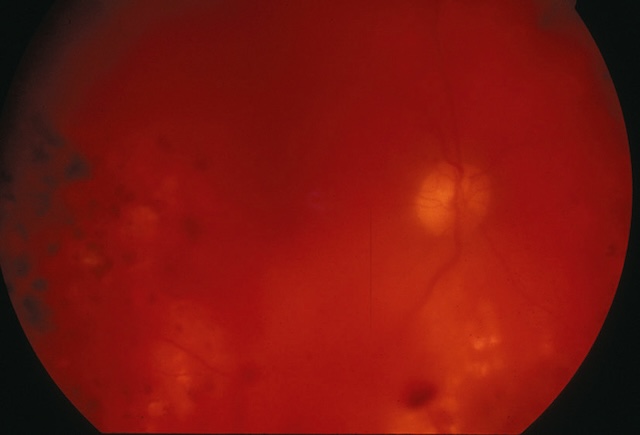

b 25Hémorragies du fond d’œil

- • les hémorragies intravitréennes (fig. 1.38 et fig. 1.39);

Fig. 1.38 Hémorragie intravitréenne modérée, laissant voir la rétine. Cette photographie en fond d’œil obtenue par examen rétinien met en évidence une hémorragie intravitréenne modérée. Bien que le vitré soit envahi partiellement par du sang, les structures rétiniennes profondes restent en partie visibles, notamment la papille optique et le trajet de quelques vaisseaux rétiniens. La diffusion du sang est irrégulière, avec des zones plus denses parsemées de plages floues rouge foncé, traduisant la présence de sang diffus dans le vitré. L'ensemble du champ visuel apparaît voilé, mais sans obstruction totale, ce qui suggère un saignement de degré moyen. Ce type de présentation est souvent associé à une rétinopathie diabétique, une déchirure ou un décollement rétinien.

Fig. 1.39 Hémorragie intravitréenne massive. Cette vue de fond d’œil obtenue par imagerie rétinienne met en évidence une hémorragie intravitréenne massive, occupant l’ensemble de la cavité vitréenne et masquant les repères habituels comme les vaisseaux rétiniens, la papille ou la macula. La surface apparaît intensément saturée de tons rouges et violacés, avec une dominance hématique homogène au centre du champ. Une légère zone plus claire, circulaire et centrée, évoque un reliquat de transparence localisée, probablement au niveau de la fovéa. L’opacité globale du vitré rend impossible la visualisation nette des structures du pôle postérieur. Cette présentation suggère une rupture vasculaire sévère dans la cavité vitréenne, potentiellement associée à une pathologie vasculaire rétinienne ou à une complication post-traumatique. L’image traduit une obstruction dense de l’axe visuel, nécessitant une prise en charge urgente.

- • les hémorragies prérétiniennes, qui masquent les vaisseaux rétiniens (fig. 1.40);

Fig. 1.40 Hémorragie prérétinienne masquant les vaisseaux rétiniens. L’examen du fond d’œil montre une large nappe rouge foncé occupant la zone centrale droite, dissimulant les vaisseaux rétiniens habituellement visibles dans cette région. Cette étendue sombre, bien arrondie et homogène, contraste nettement avec les structures avoisinantes plus orangées. On remarque que la papille optique est visible à gauche, légèrement excentrée, avec quelques vaisseaux rétiniens principaux partant de son centre. Le reste du fond d’œil conserve une coloration régulière et un réseau vasculaire identifiable, sauf à l’endroit exact où le saignement est venu se superposer. Cette image obtenue à partir d’un examen du fond d’œil évoque une accumulation de sang devant la rétine, probablement sous forme d’un voile prérétinien, rendant cette zone visuellement obstruée.

- • les hémorragies sous-rétiniennes (fig. 1.41);

Fig. 1.41 Hémorragie sous-rétinienne (ne masque pas les vaisseaux rétiniens). Sur cette photographie prise lors d’un examen du fond d’œil, on observe une large hémorragie sous-rétinienne, bien marquée au centre de la rétine. Elle s'étale de manière asymétrique autour de la macula, formant une tache foncée aux contours irréguliers, avec des nuances rouge sombre. Malgré cette accumulation de sang, les vaisseaux rétiniens qui traversent la zone atteinte restent partiellement visibles, ce qui indique que le saignement se situe en dessous de la rétine et non à sa surface. La papille optique est bien distincte sur le côté gauche de l’image, ronde et de teinte claire, ce qui confirme qu’elle n’est pas directement touchée. La configuration et la distribution du saignement orientent vers une origine vasculaire localisée sous la rétine, possiblement en lien avec une rupture vasculaire profonde ou une atteinte choroïdienne.

- • 2627les hémorragies intrarétiniennes :